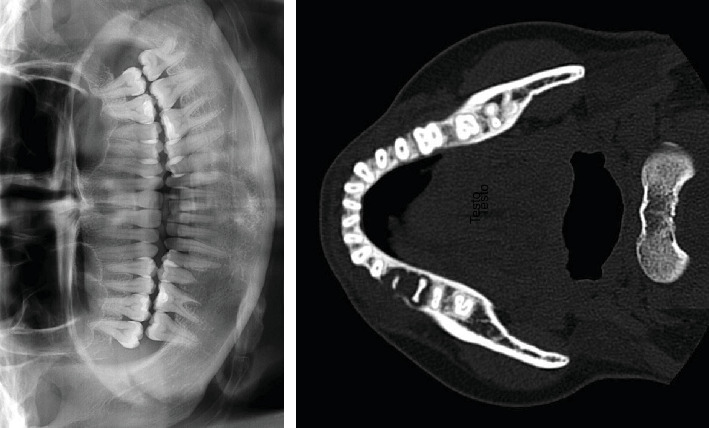

Objectives: This study is aimed at describing an unusual case of oral metastasis from colorectal adenocarcinoma and at performing a scoping review analyzing the available literature on such cases. Materials and Methods: We present a rare case of oral metastasis from colorectal adenocarcinoma in a 37-year-old Italian woman. Clinical oral examination showed the presence of a swollen lesion in the vestibular gingiva of the right mandibular region, associated with Grade III mobility of the second premolar. Radiographic examination revealed a radiolucency apical to the first molar and second premolar associated with the rhizolysis of these teeth. Furthermore, we conducted a scoping literature review of the PubMed, Web of Science, and Scopus databases in line with the Preferred Reporting Items for Systematic Reviews and Meta-Analyses extension for scoping reviews (PRISMA-ScR) guidelines. Results: The second premolar was extracted, and an incisional biopsy of the osteolytic lesion was performed for histological and immunohistochemical examination, which revealed an adenocarcinoma fragment with mucinous characteristics and a morphology and immunophenotype compatible with caudal-related homeobox transcription factor 2 (CDX2) and cytokeratin (CK) 20. In conclusion, the lesion was indicative of oral metastasis from colorectal adenocarcinoma. Furthermore, the review of the existing literature in the English language yielded 112 cases of oral metastases from colorectal adenocarcinoma, which were included in our analysis. Conclusions: Although oral metastasis from colorectal adenocarcinoma has been reported previously, it is a rare manifestation. Clinical Relevance: Because of the rarity of oral metastasis and possible variations in the clinical and histological presentations, correct diagnosis can be challenging and requires careful clinical and histopathological evaluations with adjuvant immunohistochemical studies.